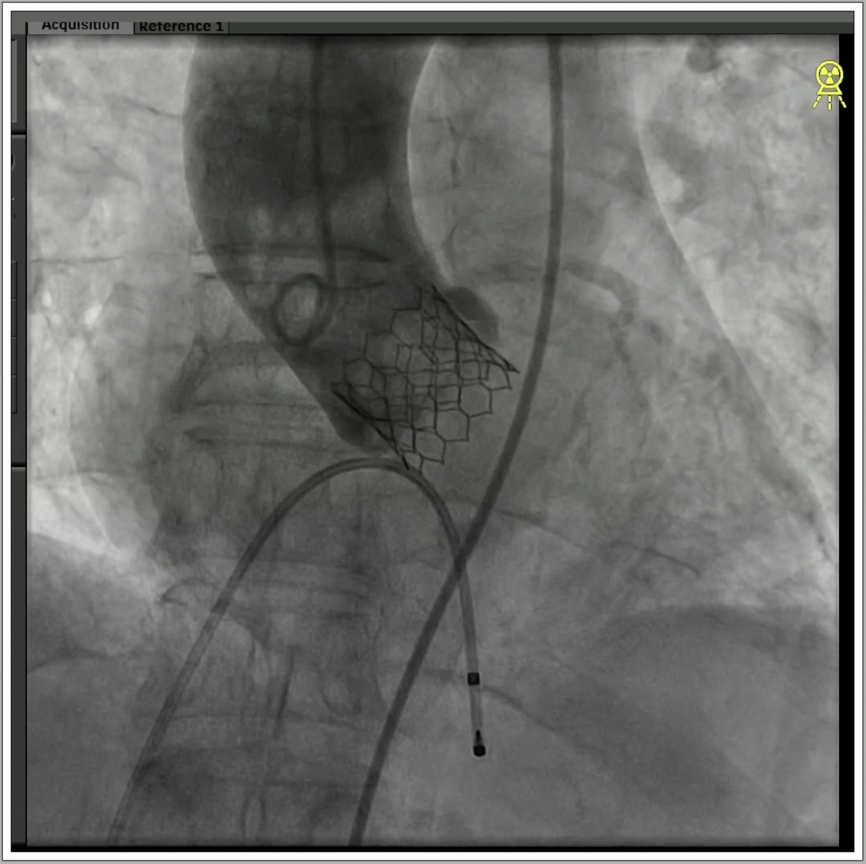

5、调整至共平面角度,瓣膜到位,快速起搏下精准释放瓣膜。

6、瓣膜植入且撤出导丝后,造影超声结果均显示瓣膜工作良好,术后导管测量压差8mmHg,经胸超声检测微量瓣周漏,手术成功。